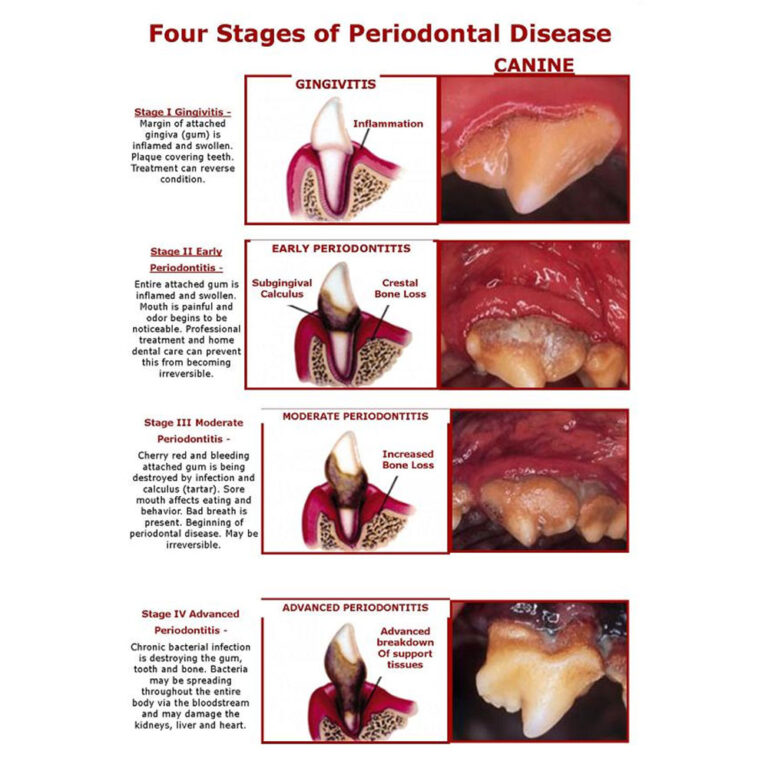

- Periodontal disease is a term used to describe the infection and associated inflammation of the periodontium (the tissues surrounding the tooth).

- Gingivitis is an inflammation of the gums caused by the accumulation of plaque.

- Then tooth scaling will be performed, using both hand and ultrasonic scalers to remove plaque and tartar above and below the gum line. The tartar below the gum line causes the most significant periodontal disease, so it is important that it be thoroughly removed.

When periodontal disease is advanced, it may not be possible to save the badly affected teeth, which may need to be extracted either during the procedure or at a later time.